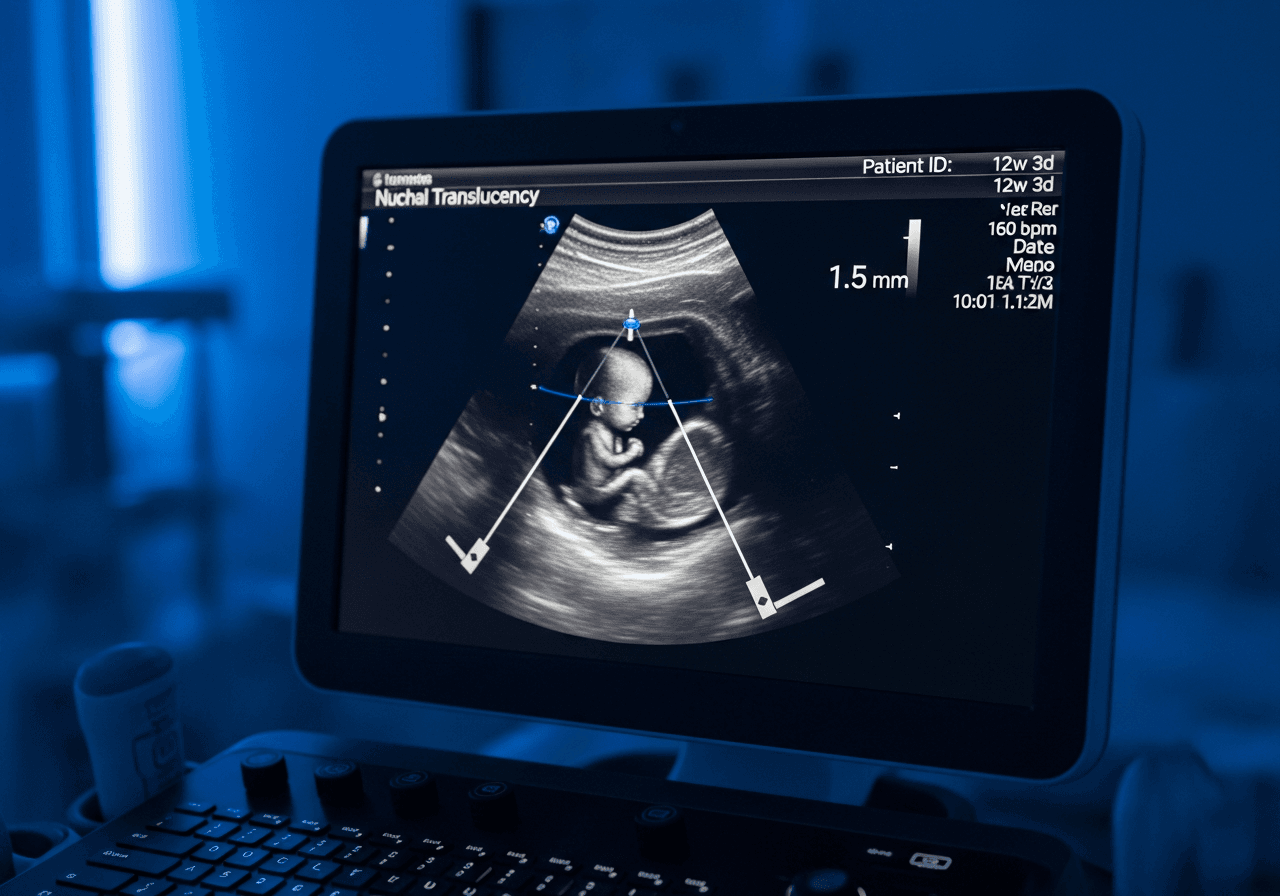

La clarté nucale : qu'est-ce que c'est ?

La clarté nucale est un espace liquidien situé à l'arrière de la nuque du fœtus. Sa mesure, combinée à l'âge de la mère et aux marqueurs sériques, permet de calculer le risque de trisomie 21. Une clarté nucale inférieure à 3 mm est considérée comme normale.

Mesure de la clarté nucale

La mesure de la clarté nucale au 1er trimestre